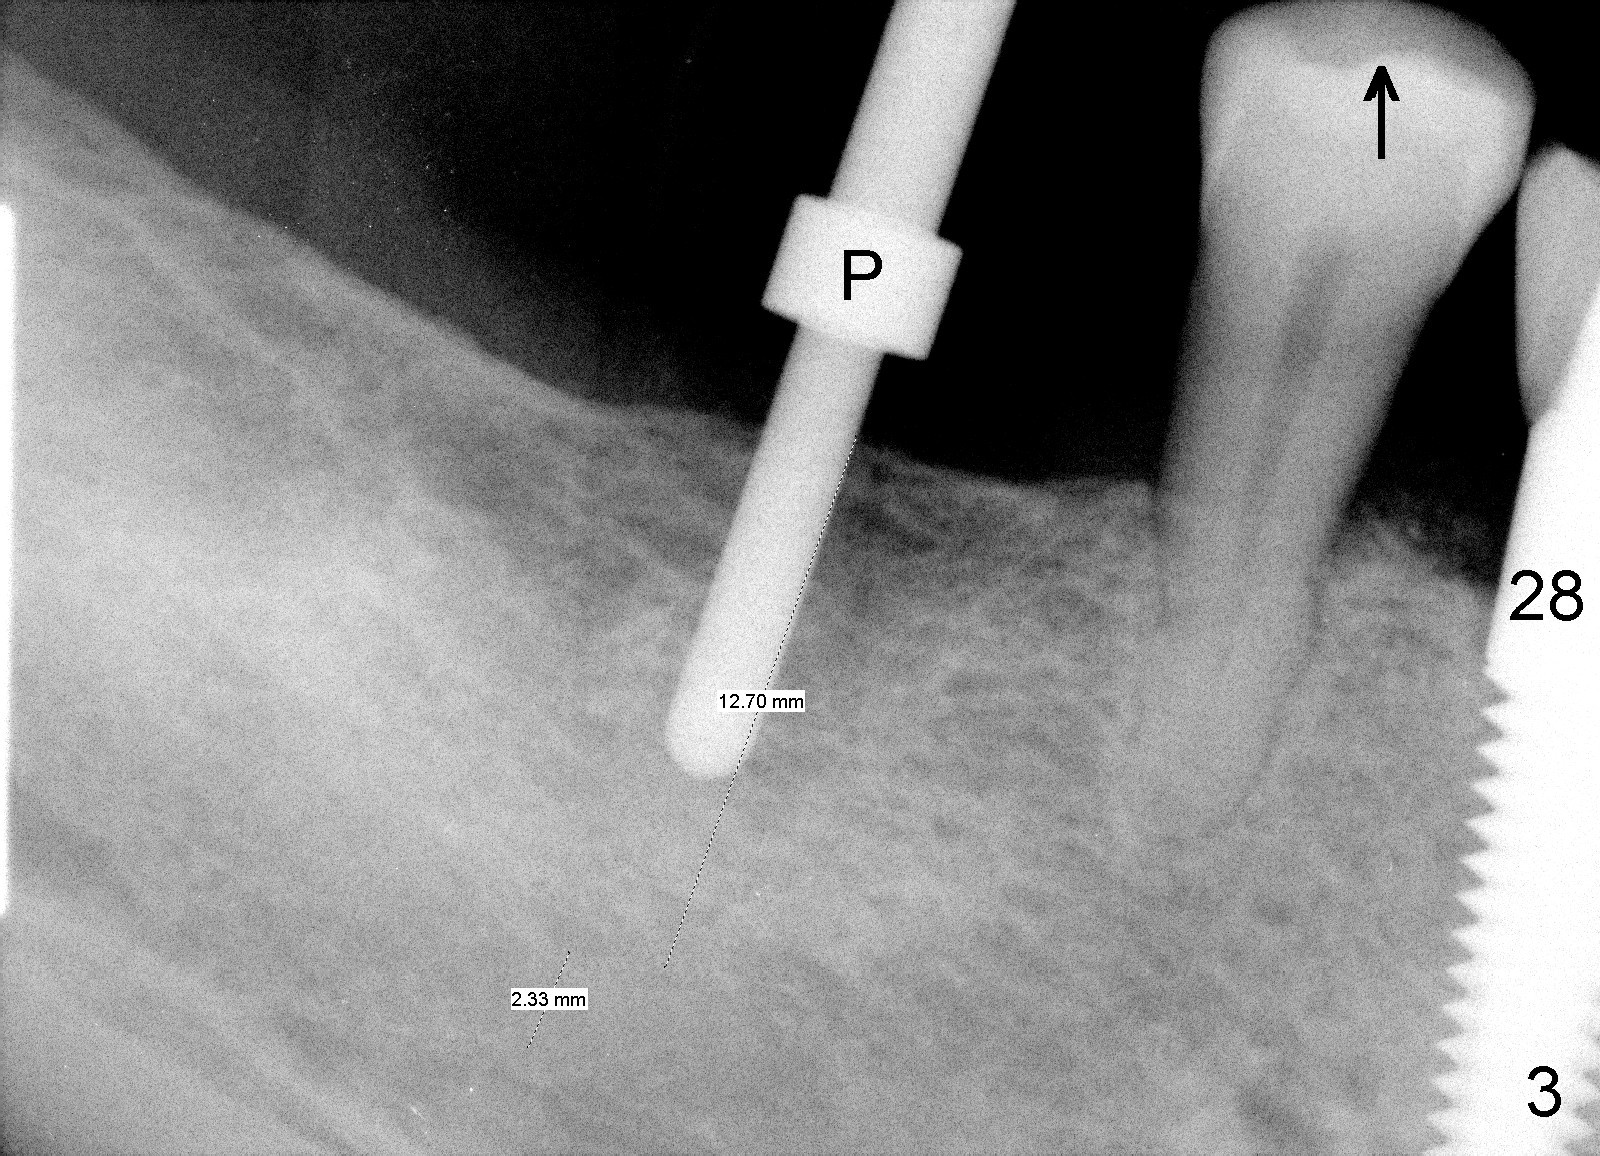

CBCT studies show that a 6x11 mm implant can be safely placed at the site of the tooth #30 (Fig.1 (coronal), 2 (sagittal section). Osteotomy is initiated by 2 mm pilot drill at the depth of 8 mm from the crest (the prospective implant is 3 mm above the crest); X-ray is taken with a parallel pin (Fig.3 P). It appears that there is 12 mm of bone from the crest to the upper border of the inferior alveolar nerve canal. The depth of osteotomy is accordingly adjusted to 11 mm below the crest; osteotomy finishes with insertion of 6x14 mm tap (Fig.4); the patient feels pressure while the tap is being inserted. Following further infiltration with Lidocaine, the depth of the osteotomy is intended to increase in order to bury the implant deeper, because the coronal portion of the buccal plate starts to perforate. The patient feels pain. Finally a 6x14 mm implant is placed ~ 1 mm above the inferior alveolar canal (Fig.5). As mentioned earlier, the rough surface of the implant is exposed buccally (Fig.6 between arrowheads). The nearby buccal plate is decorticated (Fig.7). The autogenous bone harvested during osteotomy (Fig.8) is going to be placed over the exposed portion of the rough surface of the implant (Fig.9); the graft is covered by collagen dressing (Fig.10). The buccal and lingual flaps are approximated with sutures mesial and distal to the implant (Fig.11). To increase the retention of perio dressing, a 4x3 mm abutment is placed.

Placement of implant at the site of #30 is a part of full mouth reconstruction aided by orthodontic treatment (1). As Fig.3 demonstrates, the tooth #29 is supraerupted (arrow). Once the implant at the site of #30 is osteointegrated, it is used as one of anchorages (the other is #28 implant crown) to intrude #29. In fact, the patient is uncooperative in orthodontic treatment. There is cortical bone-like formation 3 years postop, 1 year 10 months post cementation (Fig.12 <). There is no bone loss 2 year 11 months post cementation (Fig.13 CT).